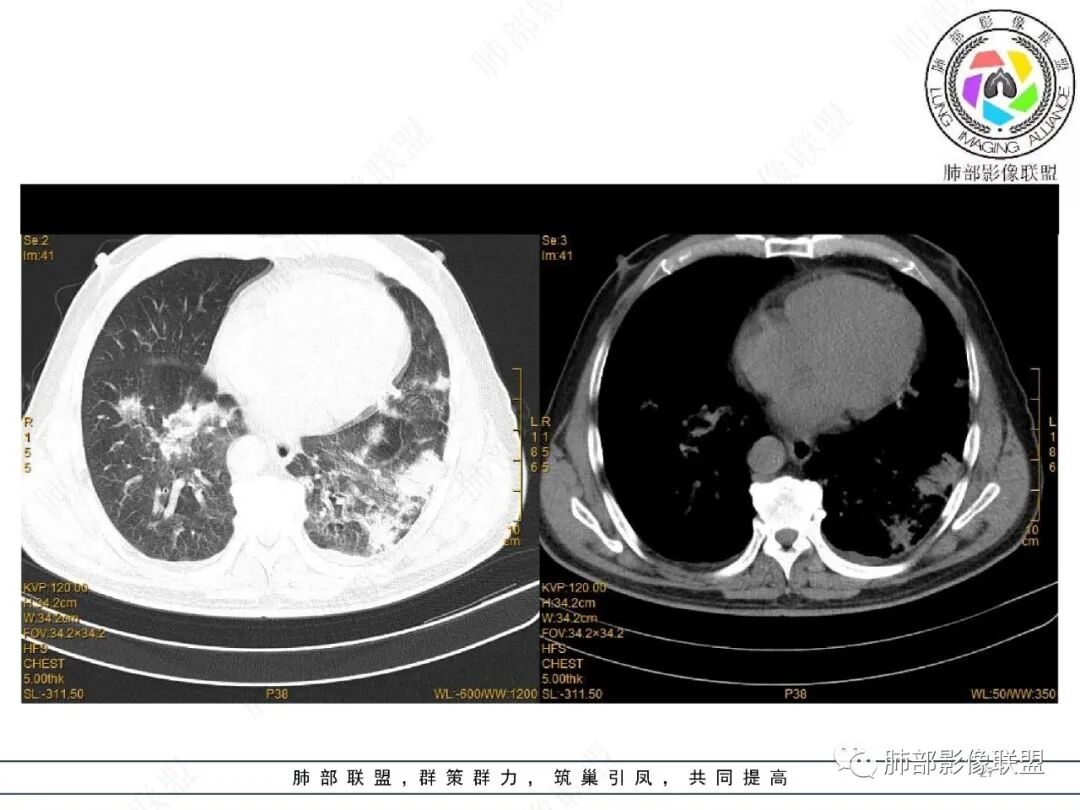

2022.2.17CT显示两肺中内带多发结节影、斑片影、条索影,部分病灶侧向融合与胸膜平行。部分病灶沿着支气管血管束分布、其内支气管稍扩张。部分病灶呈反晕征。大部分病灶边界显示清晰,部分病灶周围可见边界不清的GGO。2022.4.12CT显示两肺中内带多发结节影、条索状、条带状高密度影,边界收缩平直凹陷,大部分病灶沿着支气管血管束分布,亦有位于胸膜下侧向融合与胸膜平行的病灶。总体与第一次CT对比两肺病灶明显吸收。

3、病例小结:

老年男性,两肺多发病灶,整体呈OP样改变,至于是原发性还是继发性的OP,需要临床鉴别。此病例穿刺结果是隐球菌。该病例CT上缺乏隐球菌典型的“在那遥远的胸膜下,多个蘑菇兄弟,可以侧向融合呈长串状与胸膜平行”影像表现,更多是OP样改变,仅凭临床表现或影像资料诊断隐球菌难度比较大。当然也不除外二元论,导致隐球菌的影像表现被掩盖。